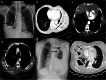

Figures